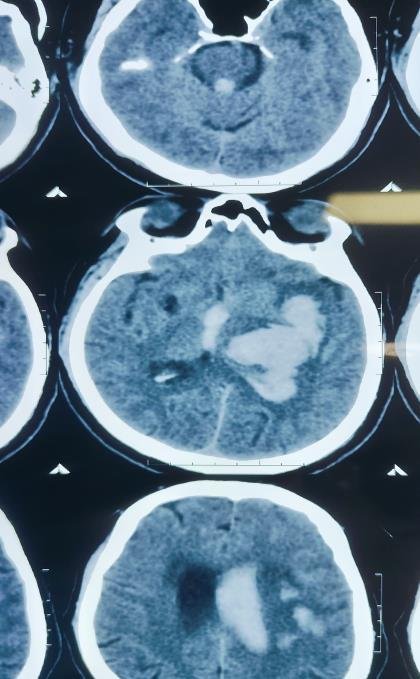

CT Scan Findings

Acute large intraparenchymal bleed in the left gangliocapsular region, corona radiata, and left fronto-parietal lobe.

Size: 41 × 57 × 60 mm (CC × AP × TR).

Mild perilesional edema causing mass effect with 6.7 mm midline shift to the right.

Intraventricular extension of bleed into both lateral ventricles, third, and fourth ventricles.

Mild periventricular ooze → suggestion of developing hydrocephalus.

Mild cerebral edema.